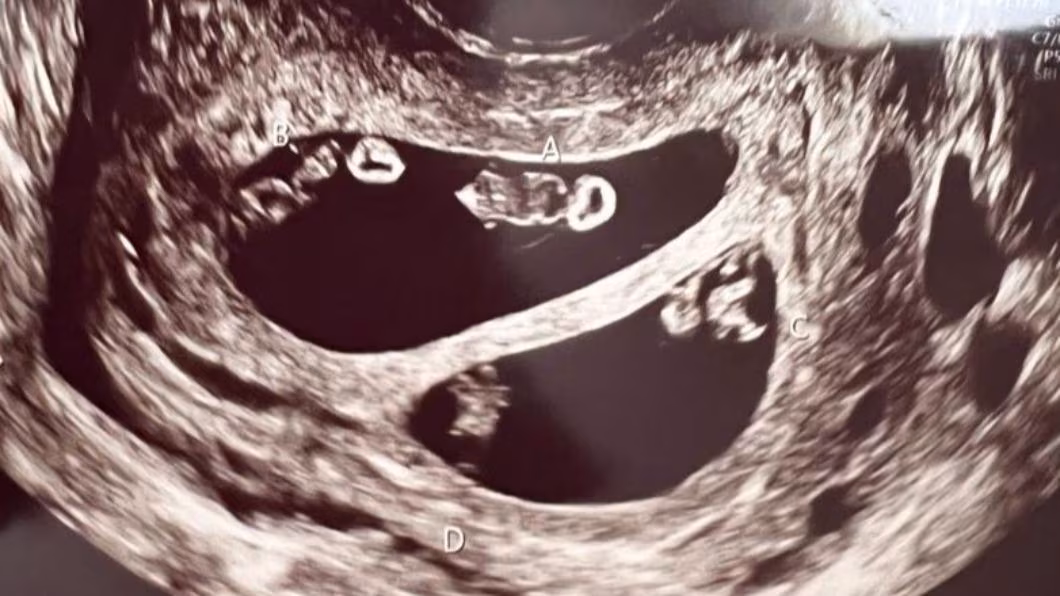

醫生在照超音波時發現驚人景象,艾希莉本來以為自己是懷著一對雙胞胎寶寶,沒想到醫生疑惑的看著螢幕好久,又走出房間請同事一起來觀察,最後才確定她竟然懷上了2對同卵雙胞胎,分別為2男2女,而醫師也解釋這狀況在醫學上發生機率僅7千萬分之一,根本就像是中了一張大樂透般不可思議!

醫生接受採訪時表示他也從來沒有見過這種案例,「我當時還走出房間上網搜尋了一下才確定」,艾希莉透露她的母親有一對雙胞胎兄弟,祖父自己是雙胞胎,姑姑則是生了一對雙胞胎,而她男朋友的媽媽也是雙胞胎,因此兩人身上或許都有著生雙胞胎的基因吧!